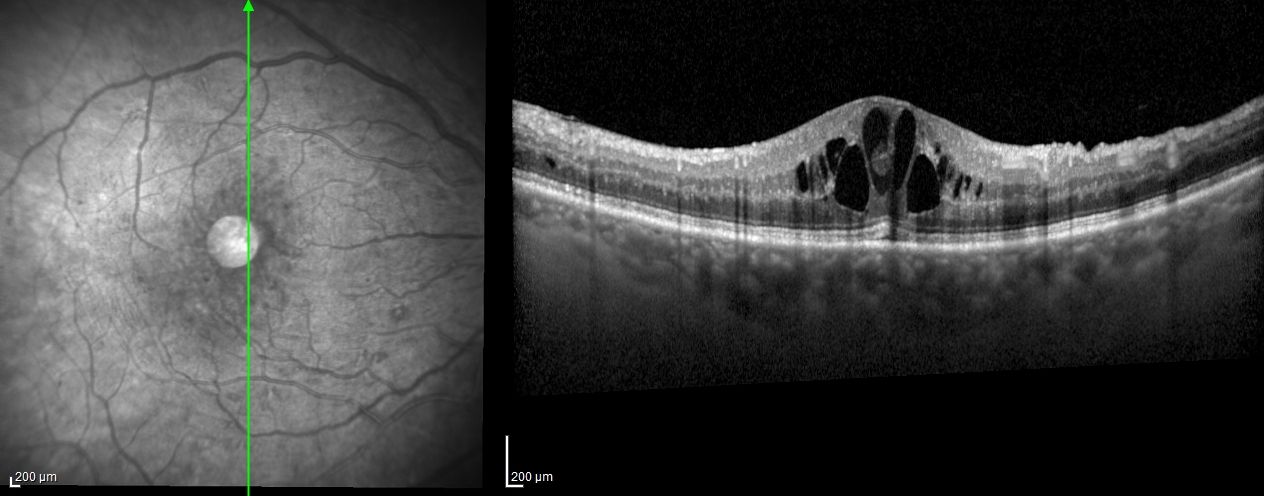

Mi prendo cura  principalmente di patologie retiniche e maculari, come maculopatia secca ed essudativa, maculopatia miopica e diabetica, fori maculari, membrane epiretiniche (pucker), distacco di retina. Gestisco inoltre patologie della superficie oculare e occhio secco, retinopatia diabetica, glaucoma, uveiti, herpes oculare, miopia, ipermetropia e occlusioni vascolari retiniche. Utilizzo le terapie più innovative, come anti-VEGF, steroidi, antibiotici e approcci chirurgici mini-invasivi.

Ascolto attentamente ogni paziente per creare un percorso personalizzato, basato su imaging avanzato (OCT, angiografia retinica, campo visivo computerizzato).